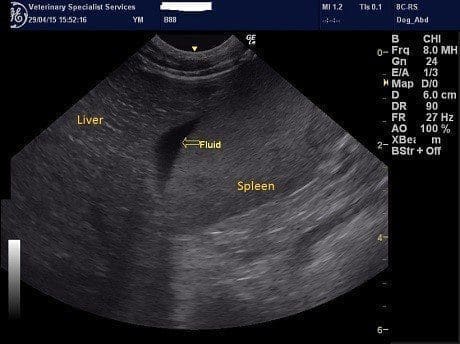

An abdominal ultrasound was performed. A small volume of free fluid was identified in small pockets. Abdominocentesis confirmed that the fluid was blood and had a similar PCV to that of circulating blood, indicating recent haemorrhage.

A large mass was identified in the mid abdomen which had variable echogenicity and areas of cavitation. Doppler suggested the mass was quite vascular. The origin of the mass was very difficult to determine due to its large size. Initially a splenic mass was considered but there was no obvious point of contact with the spleen on ultrasound. Multiple small hypoechoic masses were also noted in the abdomen consistent with enlarged lymph nodes.